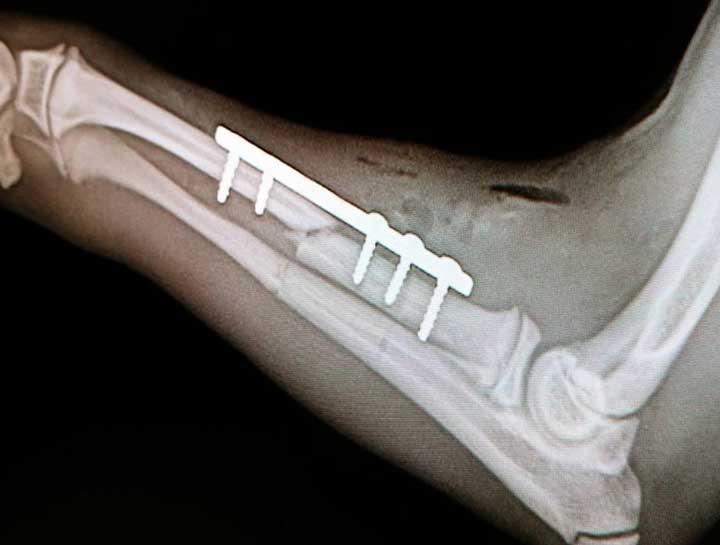

Orthopedic Pet Surgery

Cruciate, patella luxation, and hip surgery